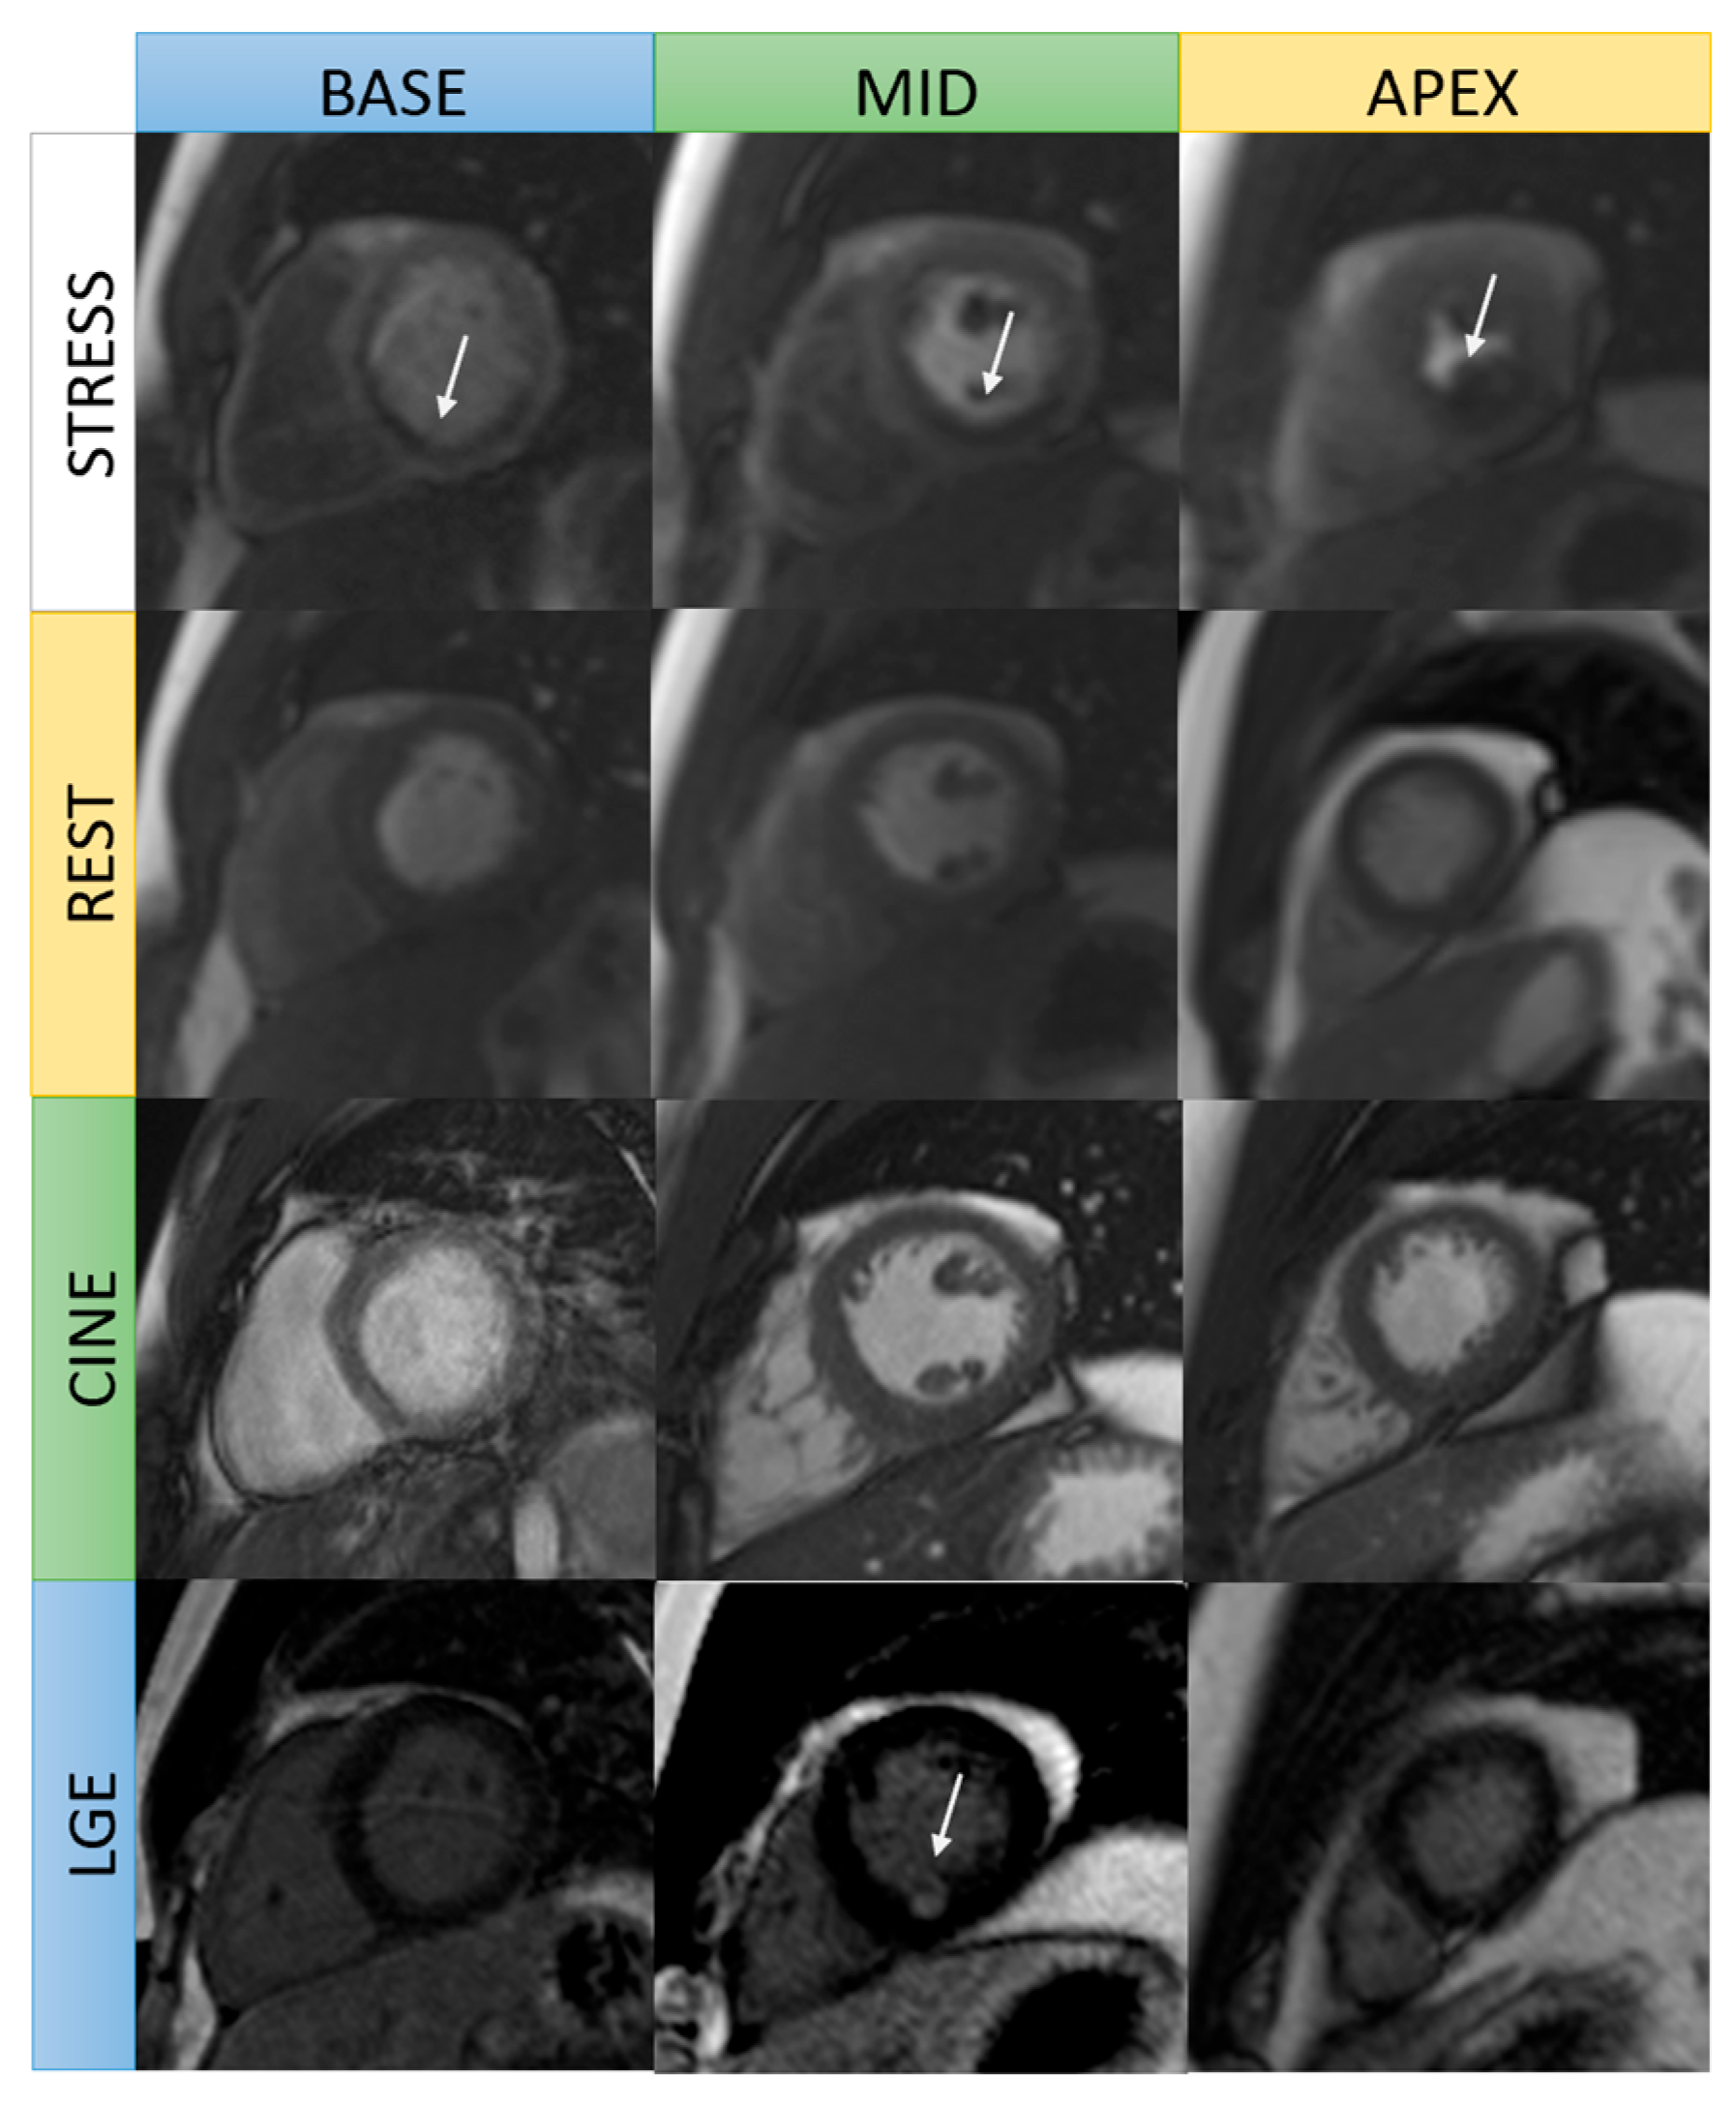

| Stress perfusion (with adenosine infusion) | Real-time cine | 3 slices short axis: basal, mid, apical LV | Detection of inducible ischemia |

| Rest perfusion | Real-time cine | 3 slices short axis: basal, mid, apical LV | Comparison to stress perfusion imaging |

| Late gadolinium enhancement (LGE) | LGE imaging: magnitude and phase sensitive inversion recovery | Short-axis stack Long axis-single slice: 2 chamber, 3 chamber, 4 chamber view | Detection of infarction or fibrosis |